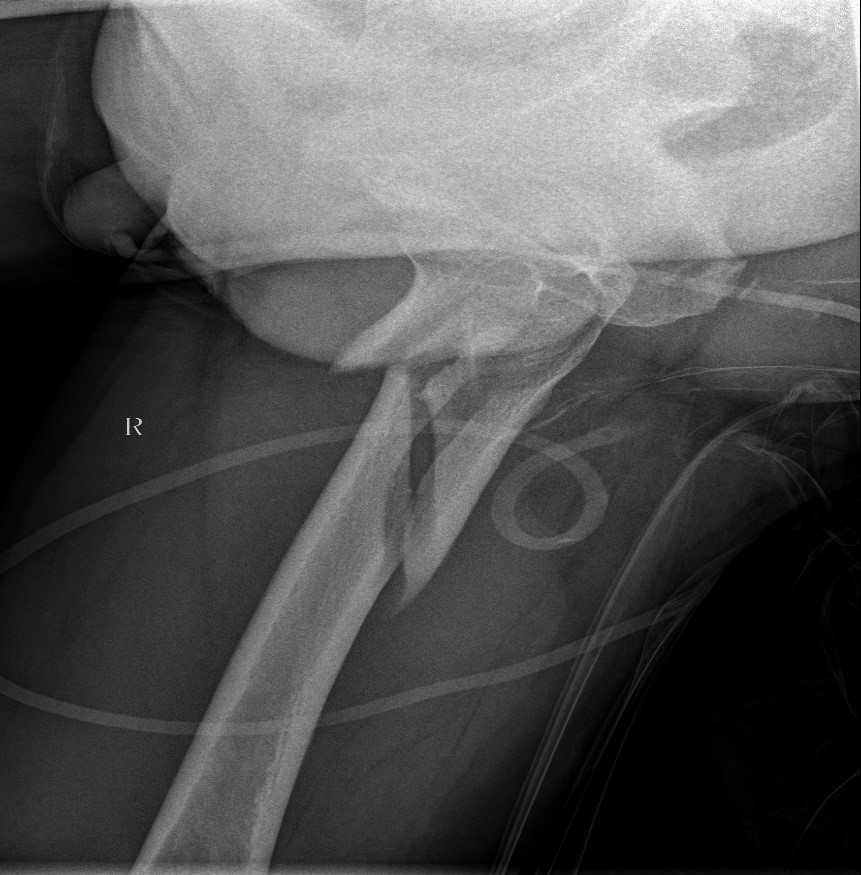

患者情况:吴女士,5年前曾在金瓶梅电影接受人工髋关节置换术,近日因在家中地板湿滑处摔倒,导致假体周围骨折。

1.摔伤后需评估假体是否松动;

2.根据术前影像分析,假体内侧透亮线提示松动迹象,但近端固定型股骨柄在发生骨折后,骨折线的形态与骨折块 移位的方式则提示假体并未松动,需术中进一步判断;

3.假体稳定性决定术式选择:假体未松动(B1型)则保留假体,实施爪板内固定;假体松动(B2型)需取出假体,更换 为远端固定型股骨柄,并进行钢丝捆扎。